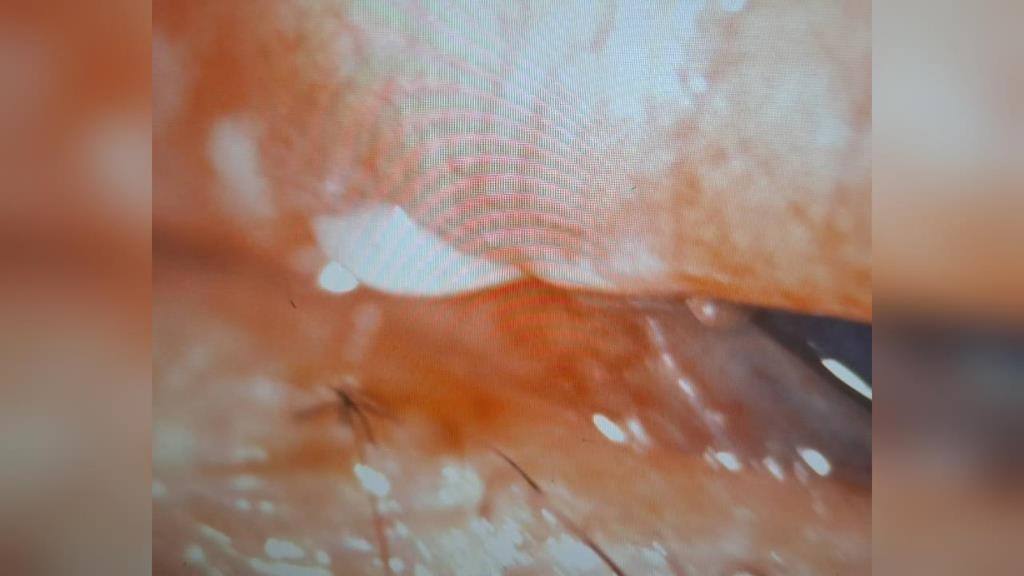

雪白瑪爾濟斯,對人撒嬌,模樣可愛,讓人不禁想伸手,抱入懷中,不過高雄有女子卻被狗狗咬傷,差點失明。女子的眼皮撕裂傷,眼結膜水腫、出血,原本以為是一般受傷,但醫師翻開眼皮一看嚇一跳,一塊白色碎片就插在上面,竟然是狗狗的牙齒。眼科醫師洪啟庭:「當下就馬上用生理食鹽水幫她洗乾淨,她還是覺得眼睛還是很脹,我們把她翻開,結果就看到這個白白的東西。」受傷的女子當天到朋友家完,看到朋友養的瑪爾濟斯很可愛,伸手抱牠,沒想到狗狗突然朝她臉部咬下去,右眼當場鮮血直流。

眼科醫師洪啟庭:「馬爾濟斯就衝向她先咬下去,那牙齒咬在那邊動啊動,結果有裂痕牙齒碎片就掉了。」0.3公分的牙齒碎片卡在眼睛,案例相當罕見,而且狗狗的牙齒有細菌,最嚴重可能引起角膜潰瘍,甚至有生命危險。愛狗人協會理事長顏幸娟:「所以不是小型狗牠就溫和沒有脾氣,狗其實在攻擊之前,牠可能有用牠身體,還有狗的語言去告訴不喜歡這樣。」愛狗協會也提醒,跟不熟悉的狗狗相處,千萬不要突然靠太近,以免驚嚇傷人,還好這次女子及時治療,已經康復。